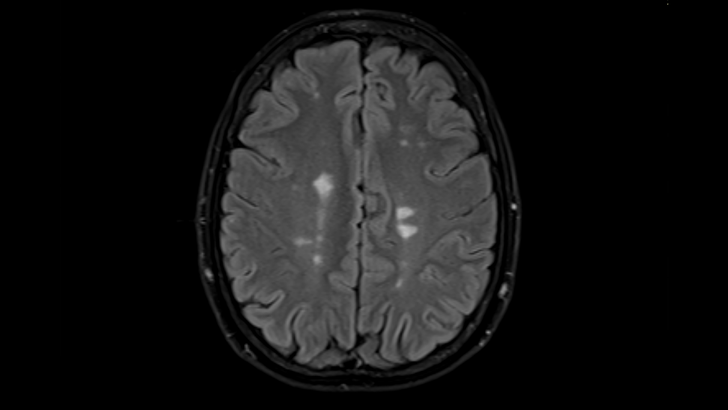

We also still use routine MRI scans though, and when someone goes off a drug, it’s very useful to continue to monitor them. It’s extremely important to continue monitoring them. And if there’s return of disease activity, then the question just becomes, “Well, how much new disease activity is concerning?” Is one small new lesion concerning, or is it maybe two or three or however many, or maybe active lesions? That’s actually an unanswered question, but probably one or even two new small lesions on your scan that occur intermittently have not really been shown to be associated with a significant change on someone’s examination, for example, five or ten years later. Three or more lesions or an active lesion clearly would be concerning, however. There’s also probably new MRI approaches that are coming out that may be helpful to show us very subtle signs of inflammation, especially compartmentalized inflammation inside the nervous system that could be different, and so in the future we’re hopeful that those will be important. But right now, the clinical indicators that are most useful in terms of defining the risks are going to be age, time since onset, and time since last new disease activity.